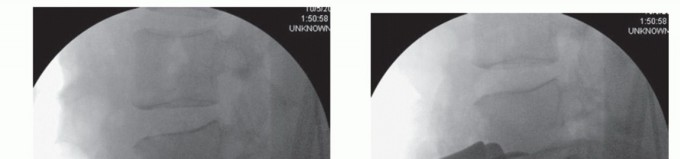

Identify the intervertebral disc and mark the midline with a spinal needle or screw placed into the vertebral body (we prefer not to place a needle into the disc space because this may create unwanted disc injury) (TECH FIG 1A).

Use AP and lateral fluoroscopic imaging to check the midline. The midline marker also serves to verify the spinal level.

The great vessels can be held in their retracted position using handheld Hohmann retractors, custom-designed pins, or Kwires, all of which can be advanced directly into the vertebral bodies (virtually eliminating the risk of vessel migration into the field of interest) (TECH FIG 1B).

- TECH FIG 1 • A. Lateral radiograph showing the spinal needle inserted into the L4 vertebral body above the L4-L5 disc to be removed. B. Lateral radiograph showing sharp Hohmann retractors placed into the L4 vertebral body above and L5 vertebral body below. Blade-type retractors can be left in place lateral to the Hohmann retractors for additional visibility, as shown.